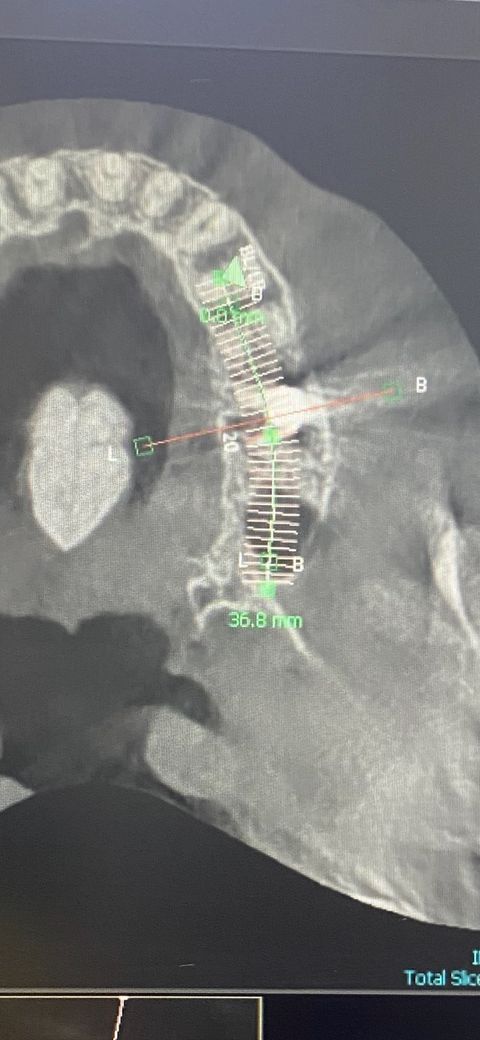

치우쳐 있는 임플란트 시간이 지나도 갠찮을까요?

지금 볼쪽으로 치우쳐잇어서 불편해서 보철 올렷다가 뺏어요, 볼쪽 잇몸이 염증이 생겨서 불편한데 보철로 커버 할수 잇다고 해서 이번에 보철 올리고도 불편한지 보자고 하거든여 ㅠ

임플란트를 할 때는 임플란트 뿌리가 잘 지지될 수 있는 치조골 안에 임플란트를 식립 하게 됩니다. 임플란트의 위치가 바깥으로 살짝 나와 있다고 하더라도 보철을 하게 되면 비정상적인 위치를 맞춰주게 됩니다.

따라서 큰 문제가 되지만 않기 때문에 임플란트를 잘 관리하면서 사용하면 될 것으로 생각됩니다.

임플란트 위치가 중요하긴 하지만, 많이 치우친건 아닌거 같으니 보철물을 잘 만들어서 사용하시면괜찮을것같습니다.